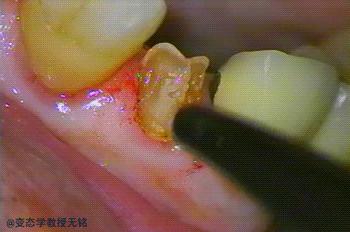

先来区分一个概念,牙神经与牙髓,理论上来说它们俩不是一回事,牙神经属于牙髓的一部分。牙髓包含神经,淋巴,血管和结蹄组织等。我们通常所说的“杀神经”是根管治疗的一个步骤,根管治疗是治疗牙髓一种比较彻底的方法,包括抽神经,根管预备,消毒,充填。

举个例子,出现牙髓炎症,根尖炎以及牙齿断裂神经外露时,如果牙齿疼痛严重,但是牙齿又有保留的必要,此时可进行“杀神经”,(有)如果仅仅是蛀牙,牙髓未受到感染,则不需要杀神经。医生也会尽量保留牙神经的。

根管治疗适应症: 不可复性牙髓炎,牙髓坏死,牙内吸收,根尖周炎,外伤牙,移植牙,再植牙,某些非蛀牙性牙体硬组织疾病(重度釉质发育不全,重度磨耗,牙隐裂)以及因其他治疗需要而牙髓正常者。